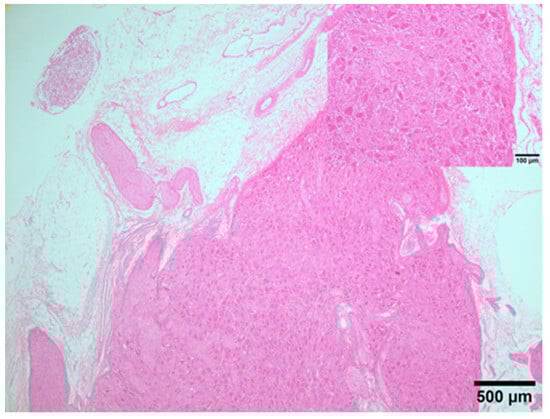

2.3. Tissue Collection, Processing, and Histological and Immunocytochemistry Studies

3.2. Gross Anatomical and Microscopic Studies